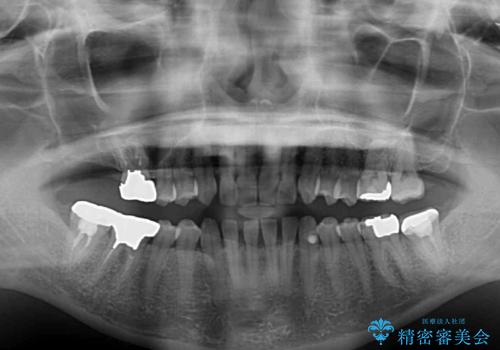

- 前歯の隙間と奥歯の目立つ銀歯を気にして来院された患者様です。

インビザラインにより下顎前歯の隙間を閉じるとともに、奥歯の咬み合わせを改善させることとしました。

矯正治療後には、銀歯のクラウンをセラミッククラウンへ替える補綴治療を行うこととしました。

左右奥歯の咬み合わせを変更させる必要があったため、治療期間は長くなることが予想されました。